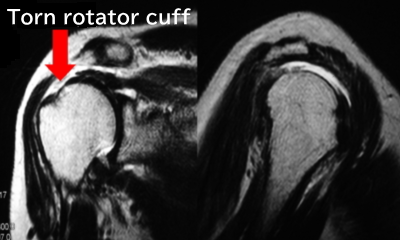

Rotator cuff tear

• Passive movement is relatively good

• Pain and catching sensation in specific positions

• Not present in multiple directions